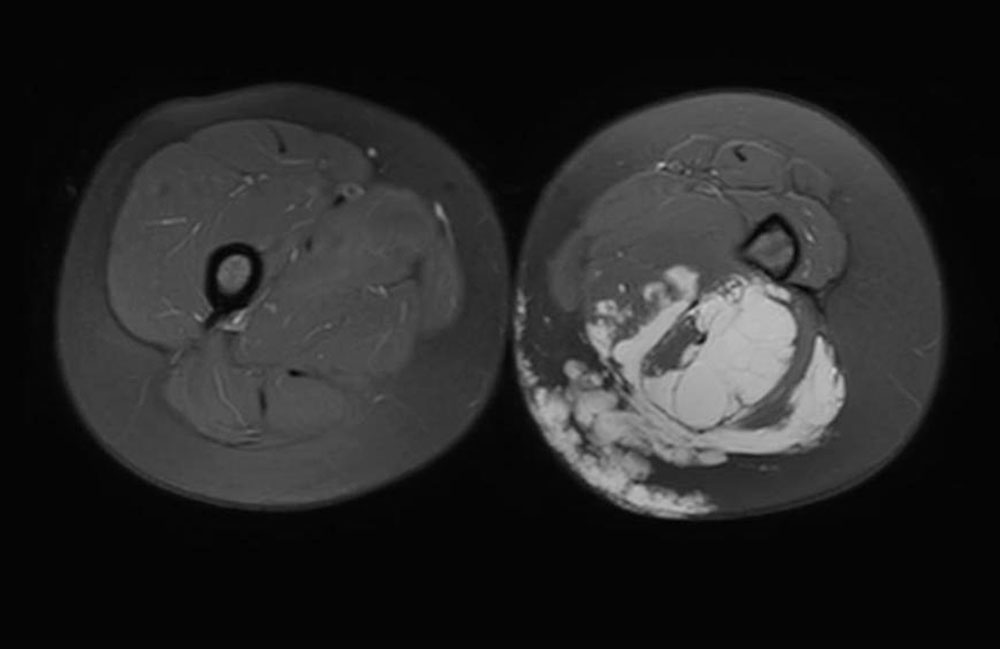

Hochgradige Ortsauflösung, guter Weichteilkontrast, dreidimensionale Bildwiedergabe und Entwicklung spezifischer Untersuchungsprotokolle für die Gewebeperfusion und Gefäßdarstellung machen die MRT zum Goldstandard in der Bildgebung der venösen Malformation. Eine Indikation dazu liegt vor, wenn die angeborene Gefässfehlbildung ausgedehnt und/oder schmerzhaft ist, also immer dann, wenn eine invasive Behandlung angestrebt wird. Ein klinisch wenig relevanter Befund erfordert hingegen nicht diese apparative Diagnostik. Insbesondere sollten Kinder keine überflüssige Untersuchung in Narkose erhalten, wenn keine invasive Therapie in Betracht gezogen wird. Neben der rechtfertigenden Indikation gehört entsprechendes Know-how bei der Auswahl der Bildsequenzen zum Gelingen der Untersuchung. Im kollegialen Gespräch zwischen Kliniker und Radiologen sollen die relevante Fragestellungen präzisiert werden, womit das passende Protokoll gewählt wird. Die Untersuchung wird ohne und mit Kontrastmittel als Magnetresonanzangiographie (MRA) durchgeführt, sodass die venöse Malformation von einer lymphatischen Malformation unterschieden werden kann, da diese kein Kontrastmittel speichert. Wie oben beschrieben, werden zudem Ausdehnung im Gewebe und Morphologie des Venensystems erfasst. Eine venöse Malformation ist in der T2-Wichtung stark hyperintens (weiß), gerade auch nach Fettunterdrückung. In der nativen T1-Wichtung stellt sie sich hypointens, ähnlich wie Muskulatur dar. Nach Kontrastmittelgabe zeigt sie ein langsames, aber praktisch vollständiges Enhancement der Läsion.